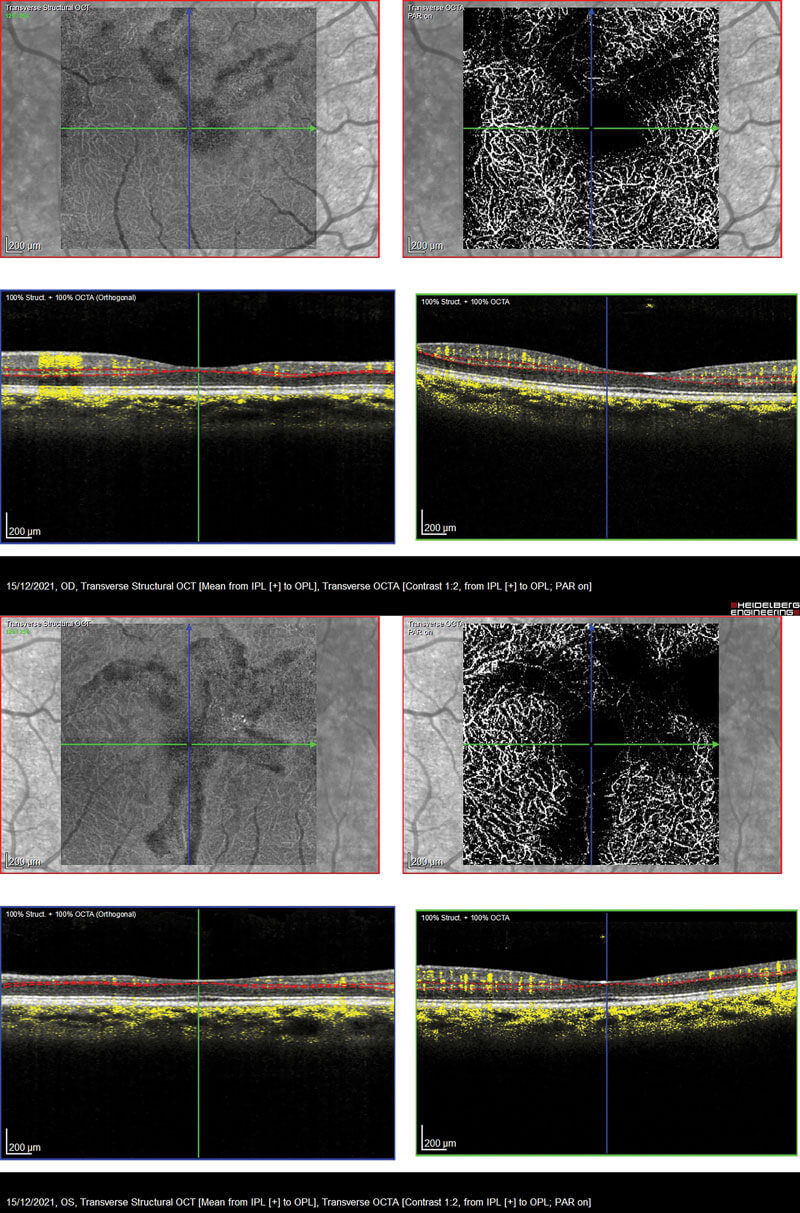

The OCT’s of the RE and LE are shown in Figure 2. Both eyes show macular thinning in the nerve fibre layer leading into the inner nuclear and plexiform layers. The RE demonstrates irregularity in the foveal avascular zone. This is highlighted by how the layers thin out from the fovea towards the temporal arcade which corresponds to the Optos images with the ischaemia. Figure 3 shows the retinal thickness maps, and this thinning can be seen easily from the maps illustrated by the violet colour and the differential in the patterned ripple indentation line. The OCTA’s in Figure 4 highlight some capillary dropout shown in the deep capillary plexus within the foveal avascular zone, which could lead to some visual loss. This area should show capillaries, but the blackened area indicates the dropout which ties in with the retinal thickness map.

Figure 4: Both eyes showing capillary dropout within the foveal avascular zone

in the deep capillary plexus highlighted by the blackened area in the OCTA.